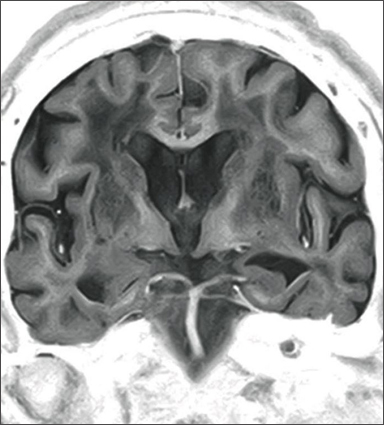

3D-GEIR

This function offers high-speed T1WI imaging through Gradient Echo with IR pulse. This allows high contrast, 3D, high spatial resolution images to be acquired. This function can be used for measurement of volume data when imaging the head.